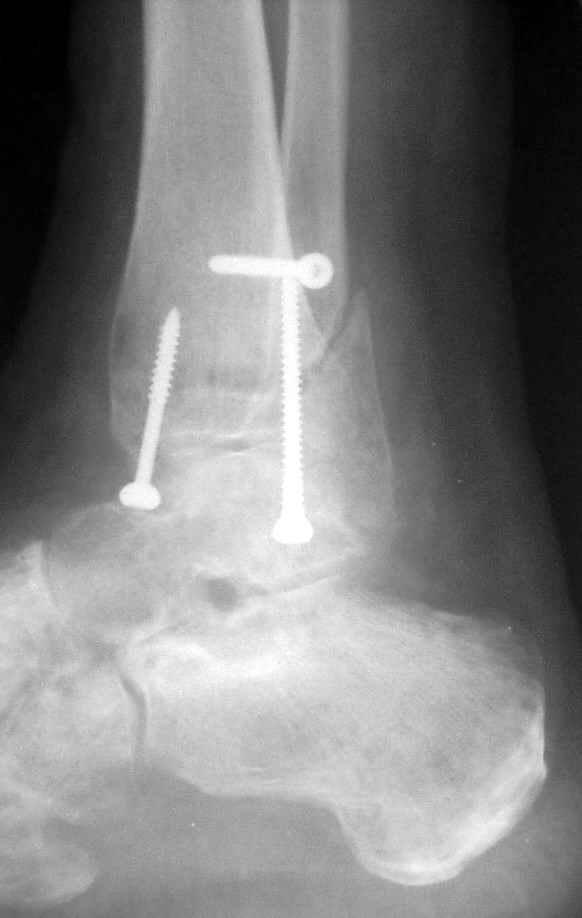

Ниже рентгенограммы

До операции 28 июля

Через месяц